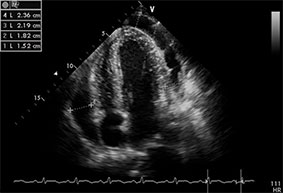

Épanchement péricardique

Le diagnostic est fait devant l’existence d’un simple décollement des deux feuillets péricardiques ou d’un épanchement péricardique qui apparaît sous la forme d’un espace clair vide d’écho (cf. fig. 20.2 et fig. 20.3). L’échocardiographie apprécie l’abondance, la topographie et la tolérance hémodynamique de l’épanchement péricardique et confirme le diagnostic d’une éventuelle tamponnade.

Fig. 20.3. Épanchement péricardique circonférentiel abondant.